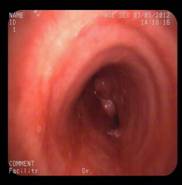

患者施某,男,49岁,1月前不明原因出现咳嗽、咯血,3月初入住我科,经支气管镜检查发现:气管近隆突处新生物,导致左右主支气管狭窄,尤其右侧明显,气管镜不能伸入。病理诊断:透明细胞肌上皮瘤。属罕见气管肿瘤,呈低度恶性。患者资料由家属送至上级医院会诊及我院全院讨论,无手术指征,因患者气道狭窄严重,随时可能因肿瘤增大出现呼吸困难及窒息,放化疗治疗因风险大暂不宜进行。我科于3月19日下午在DSA室行Y形气管支架植入术。术中,俞万钧主任负责介入操作,麻醉科严国章主任负责全麻、喉罩辅助通气及监护、DSA马霁波主任配合定位及支架释放,支架放置顺利完成,患者清醒后安返病房。

术中照片